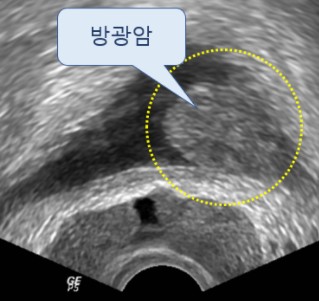

- 혈뇨 (소변에 피가 섞임)

- 설명: 암이 요도 주변이나 방광 쪽으로 침범하거나 전립선 내에서 출혈이 발생하면 소변에 피가 섞여 나오는 혈뇨가 발생할 수 있습니다. 혈뇨는 전립선암 외에도 방광암, 신장 질환 등 다양한 원인으로 발생할 수 있으므로, 육안으로 피가 보이거나 소변 검사에서 혈뇨가 확인되면 즉시 정밀 검사가 필요합니다.